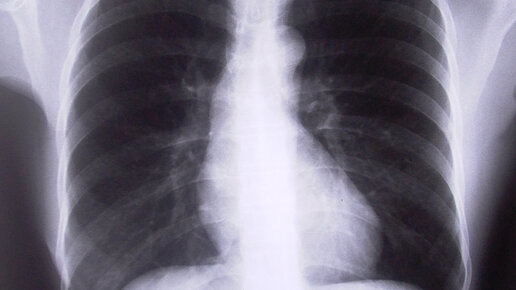

Флюорография органов грудной полости - рентгеновский метод диагностики заболеваний легких и органов грудной клетки, при котором изображение объекта переносится с флюоресцирующего экрана на фотопленку небольших размеров. Выделяют мелкокадровую (например, 24×24 мм или 35×35 мм) и крупнокадровую (в частности, 70×70 мм или 100×100 мм) методики. Последняя по диагностическим возможностям приближается к рентгенографии, но очень далека от нее. В лечебных учреждениях у ряда пациентов с заболеваниями органов дыхания флюорография может заменять рентгенографию, особенно при повторных исследованиях...

Флюорография входит в список исследований, которые нужно обязательно проходить ежегодно. Узнаем, почему есть такая необходимость и не вредно ли это. Флюорография представляет собой современное исследование органов грудной клетки с применением рентгеновских лучей. Методика позволяет быстро и достоверно определить наличие заболеваний легких, в частности, пневмонии и туберкулеза. Зачем нужна флюорография Ежегодно проходить флюорографию должен каждый, если для этого нет противопоказаний. Не проводят...